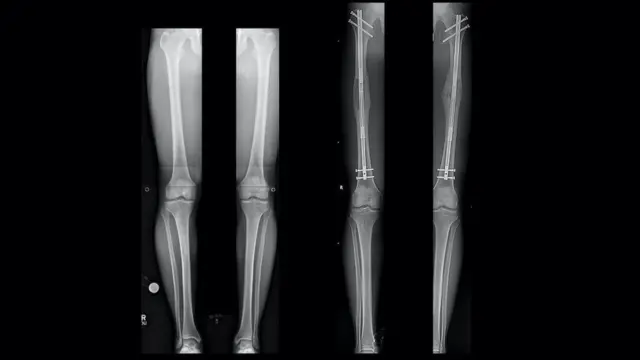

కాళ్లల్లోని ఎముకలకు రంధ్రం చేసి, వాటిని రెండుగా విడదీస్తారు. తరువాత వాటి మధ్య లోహంతో చేసిన ఒక రాడ్ను అమర్చి, కావలసిన పరిమాణానికి చేరుకునేవరకూ ప్రతి రోజూ దాన్ని ఒక్కో మిల్లీ మీటర్ చొప్పున పెంచుతూ ఉంటారు. ఇది సుదీర్ఘమైన ప్రక్రియ.

అనంతరం, చికిత్స చేయించుకున్న వ్యక్తి పూర్తిగా కోలుకోవడానికి కొన్ని నెలల పాటు థెరపీ చేయించుకోవల్సి ఉంటుంది.